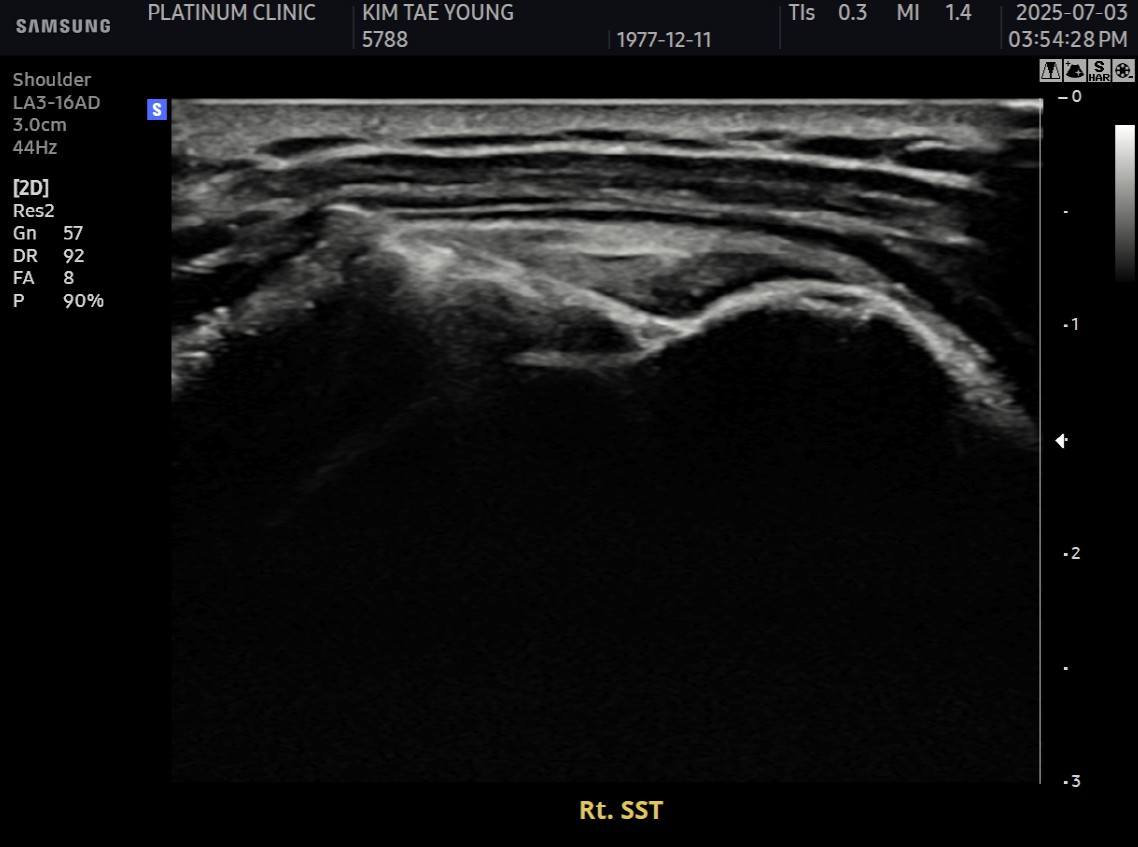

MRI와 초음파 검사 결과:

진단 결과:

- ✓관절면측 부분파열: 약 50%

- ✓점액낭면측 부분파열: 약 35%, 인대 얇아짐 동반

- ✓25년간 반복 사용으로 인한 퇴행성 변화 동반

양쪽 모두 손상된 복합 파열이었습니다.

- ✓관절면측: 봉합 부위 안정적 유지

- ✓점액낭면측: 인대 두께 4.8mm → 6.5mm (1.7mm 증가)